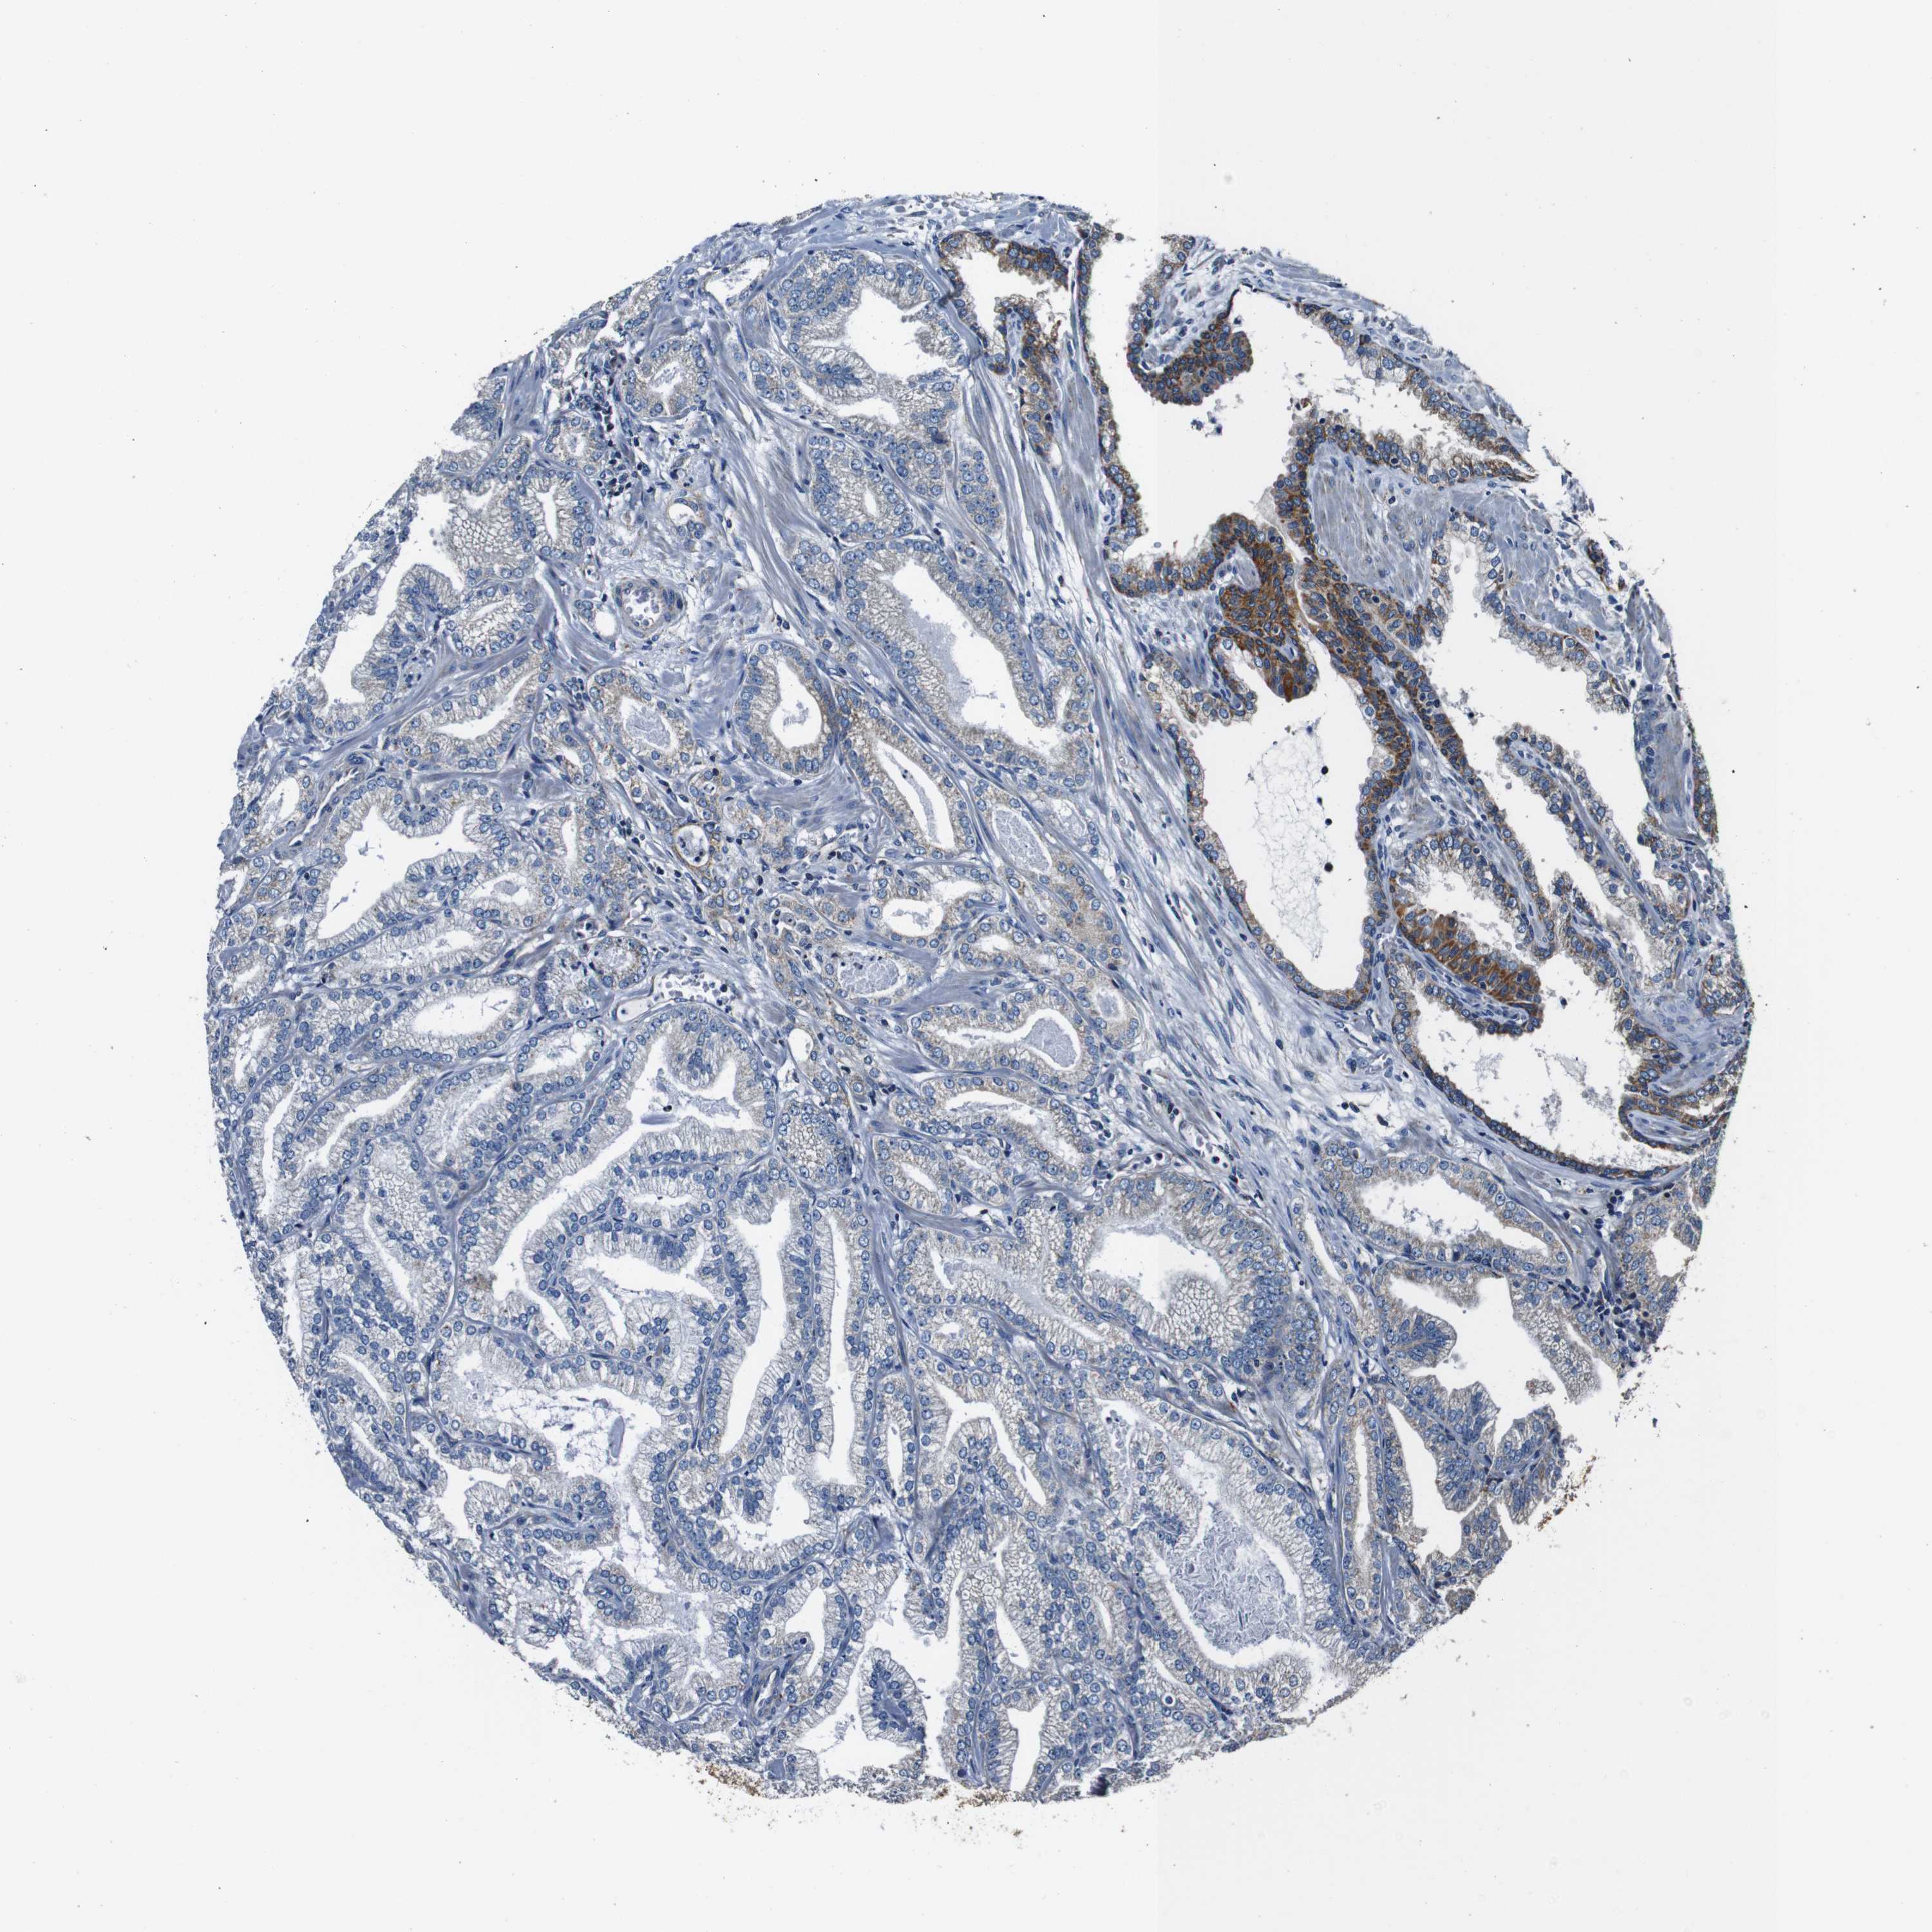

PROSTATE CANCER - Protein expressioni

A mouse-over function shows sample information and annotation data. Click on an image to view it in a full screen mode. Samples can be filtered based on level of antibody staining by selecting one or several of the following categories: high, medium, low and not detected. The assay and annotation is described here.

Antibody stainingi

Antibody staining in the annotated cell types in the current human tissue is reported as not detected, low, medium, or high, based on conventional immunohistochemistry profiling in selected tissues. This score is based on the combination of the staining intensity and fraction of stained cells.

Each image is clickable and will lead to virtual microscopy that enables deeper exploration of all samples and also displays staining intensity scores, fraction scores and subcellular localization as well as patient and tissue information for each sample.

Antibody HPA007043

Antibody HPA007044

Antibody CAB010052

Staining

High

Medium

Low

Not detected

Intensity

Strong

Moderate

Weak

Negative

Quantity

>75%

75%-25%

<25%

None

Location

Nuclear

Cytoplasmic/membranous

Cytoplasmic/membranous,nuclear

Adenocarcinoma, Low grade

Adenocarcinoma, High grade